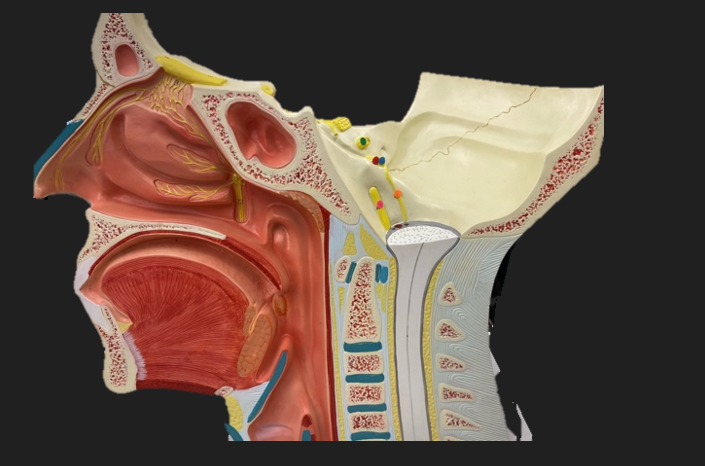

green dot

spinal nerve

orange dot

ventral root

pink dot

dorsal root

blue dot

dorsal root ganglion

red dot

dorsal ramus

yellow dot

ventral ramus

purple dot

anterior median fissure